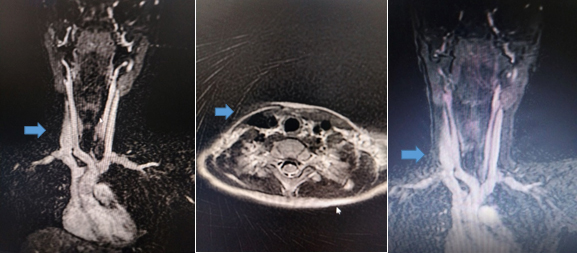

Leva unutrašnja jugularna vena urednih karakteristika. U

bolničkim uslovima učinjena magnetna rezonaca magistralnih krvnih

sudova vrata gde se evidentira desna unutrašnja jugularna vena

širacelom dužinom maksimalnog dijametra do 11 mm, leva unutrašnja

jugularna vena smanjenog dijametra do 4 mm. Jugularne vene su

prolazne, bez znakova tromboze (MR slika 4).

Slika 4 : (MR) Magnentna rezonanca sa kontrasnom

angiografijom i venografijom magistralnih krvnih sudova

vrata-flebektazija desne unutrašnje jugularne vene